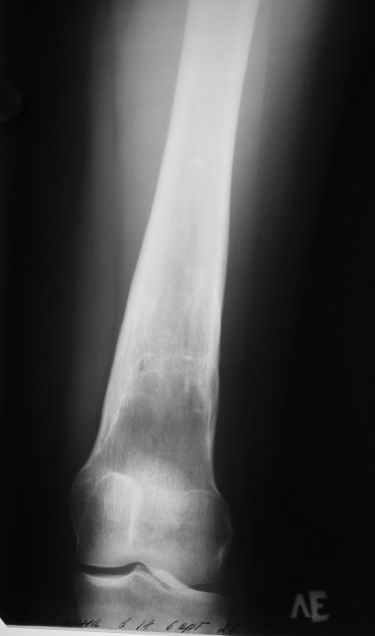

Пациентка 23 лет, доставлена в клинику с Диагнозом: Закрытый сегментарный оскольчатый перелом левой бедренной кости в верхней и средней трети. Травма в результате ДТП 10.03.2006г. Из анамнеза у пациентки диспластический левосторонний коксартроз, S-образный сколиоз 2ст. В 1999г в Кургане выполнялась остеотомия бедра в нижней трети и коррекция укорочения конечности на 3 см (рентгенограммы бедра и таза до травмы в приложении). До получения травмы пациентка ходила без боли с полной нагрузкой на левую ногу. Учитывая дисплазию левого ТБС, пациентке, вероятно, предстоит операция тотального эндопротезирования лев ТБС, что требует анатомичного восстановления проксимальногоотдела бедра. Рассматриваются следующие вариант остеосинтеза:1) Экстракортикальный остеосинтез проксимального и дистального перелома пластиной с угловой стабильностью типа LISS( г Рыбинск); 2) Ретроградный интрамедуллярный блокированный остеосинтез дистального перелома и накостный синтез проксимального пластиной с угловойстабильностью; 3) Остеосинтез бедра в аппарате внешней фиксации с фиксацией таза и возможной открытой адаптацией фрагментов. Хотелось бы узнать Ваше мнение. С уважением Украинский Евгений, г.Краснодар, ККБ N1, ТОО N3.

Судя по снимкам до перелома, большой вертел располагался высоковато. Может, подумать о том, чтобы при остеосинтезе его переместить дистальнее и/или латеральнее? Что скажут коллеги, активно занимающиеся эндопротезированием?